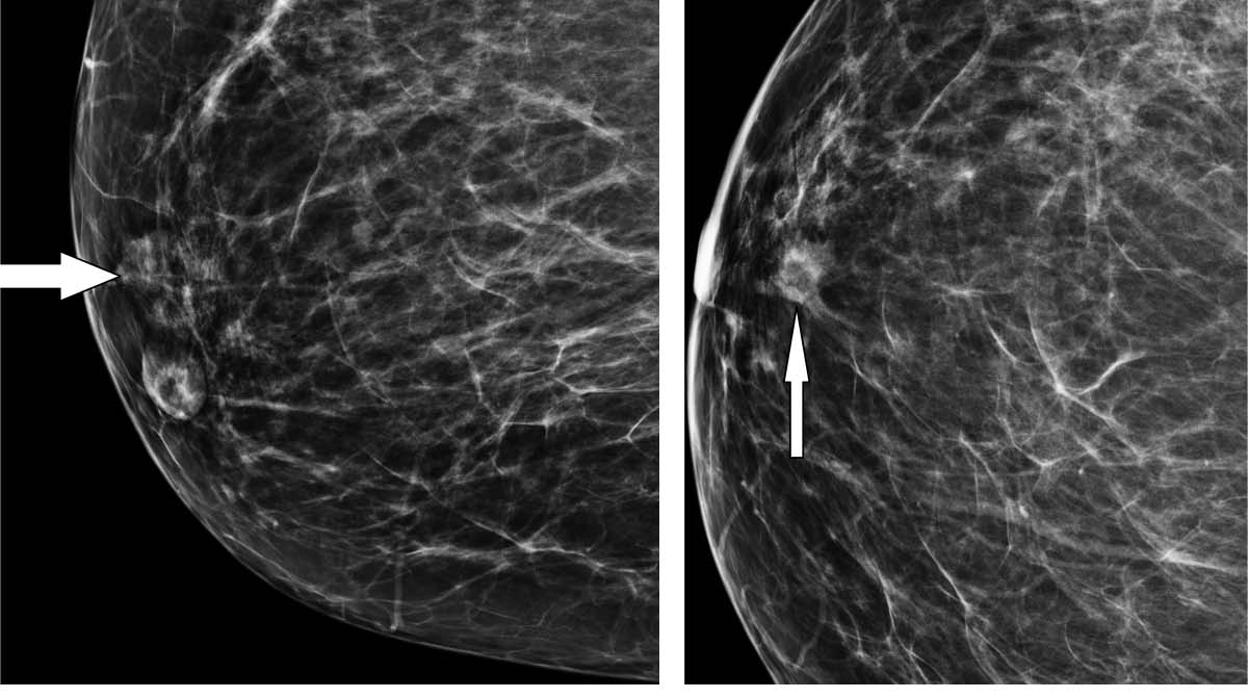

Imágenes de 3CB Radiological Society of North America

Drukker y sus colegas estudiaron recientemente una nueva técnica denominada imágenes de mama de tres compartimientos (3CB). John Shepherd y su equipo desarrollaron 3CB mientras estaba en la Universidad de California en San Francisco . Al medir la composición del tejido de agua, lípidos y proteínas en todo el seno, 3CB podría proporcionar una firma biológica de un tumor. Por ejemplo, más agua en el tejido tumoral podría indicar angiogénesis, o la producción de nuevos vasos sanguíneos, un signo temprano de desarrollo de cáncer.

Para el estudio, los científicos adquirieron mamografías de energía dual de 1 09 mujeres con masas mamarias sospechosas o altamente sugestivas de una enfermedad maligna (los tipos de lesiones en los que normalmente se realizaría una biopsia) inmediatamente antes de la biopsia, y las biopsias resultantes mostraron 35 masas que serían cánceres invasivos, mientras que las 74 masas restantes eran benignas.

Las imágenes de 3CB se derivaron de las mamografías de energía dual y se analizaron junto con la radiografía por mamografía, un método que utiliza algoritmos de inteligencia artificial para evaluar características y patrones en imágenes, algunas de las cuales son difíciles para la percepción humana, desarrollado por Maryellen L. Giger y su equipo en la Universidad de Chicago para su uso en el diagnóstico asistido por ordenador en imágenes de senos.

La combinación de análisis de imagen 3CB y radiomia mejoró el valor predictivo positivo, o la capacidad de predecir el cáncer, en masas mamarias consideradas sospechosas por el radiólogo de mama. El método combinado mejoró el valor predictivo positivo desde 32 por ciento de la interpretación visual sola a casi el 50 por ciento, con una reducción de casi el 36 por ciento en las biopsias . El método de radiografía 3CB no detectó uno de los 35 cánceres, con una tasa de sensibilidad del 97 por ciento.